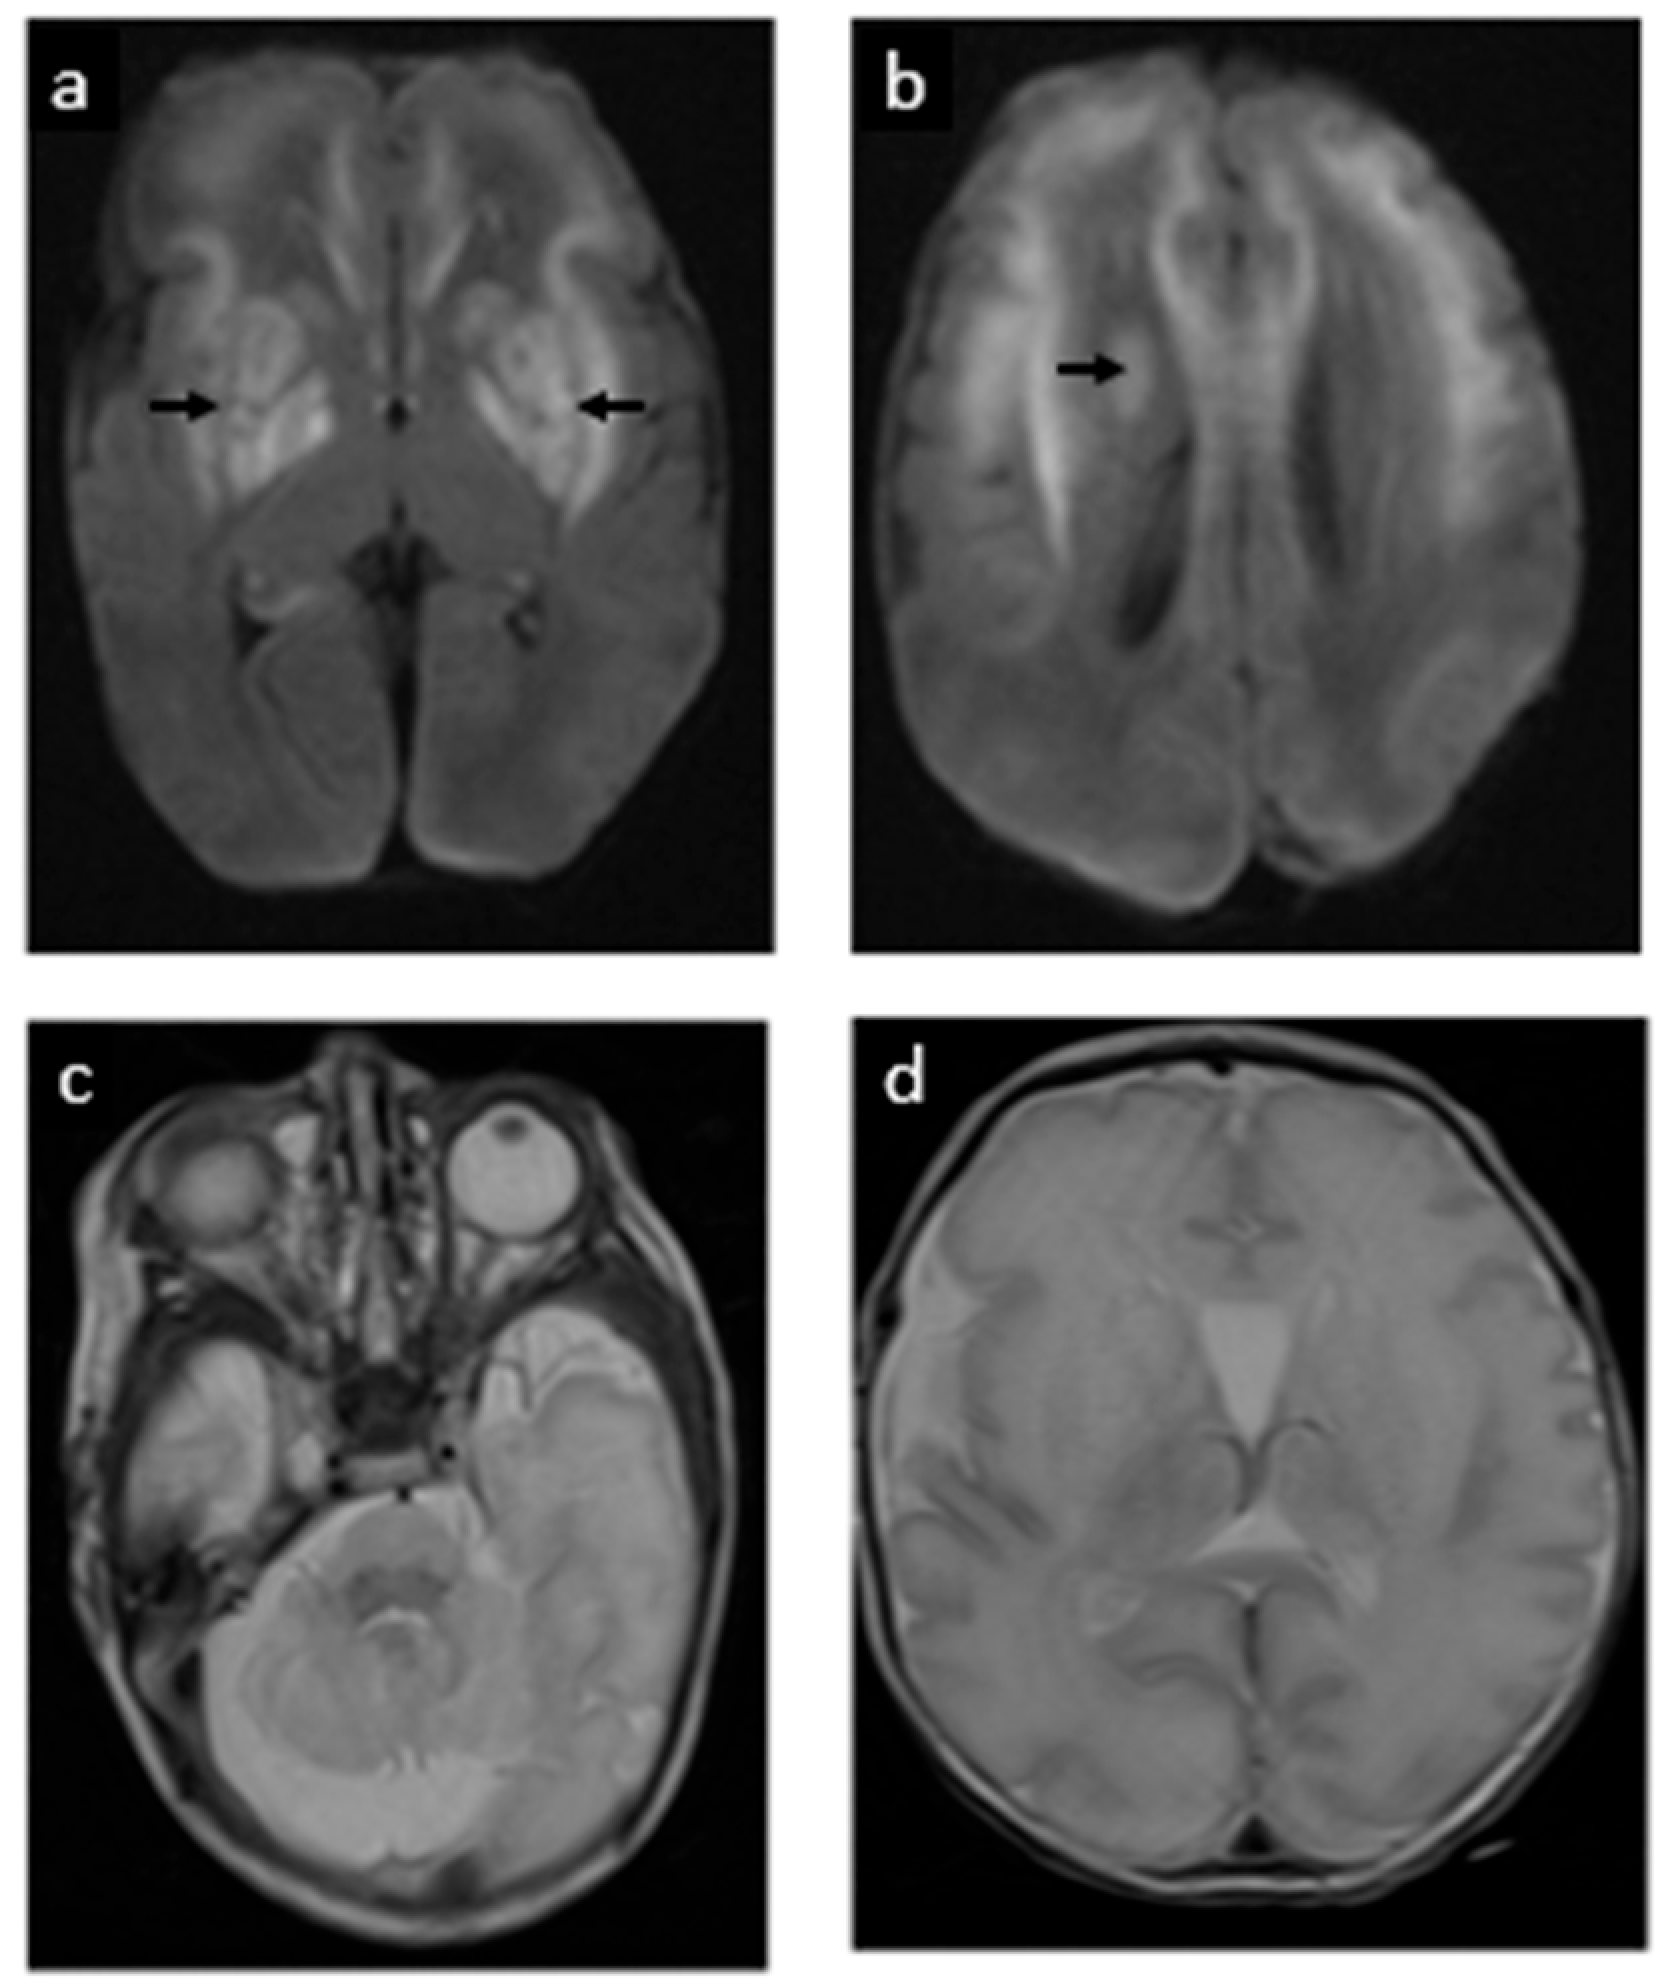

| 10 | Lubout et al., 2018 (Patient A) [10] | Yes (via chorionic villus sampling) | Fetal MRI normal until ~36 wk; then mild ventriculomegaly and subtle white-matter T2 hyperintensities observed | Day 0 (~4 h after birth) | 36 + 4 w | Neonatal seizures controlled; at 41 mo ~30–35 mo developmental level (Bayley ~16th percentile) with persistent macrocephaly (HC > P98; familial trait) |

| 11 | Lubout et al., 2018 (Patient B) [10] | Yes (via amniocentesis at 32 weeks) | Fetal MRI from 32 wk: mega cisterna magna with slightly small cerebellum; by 36 wk mild ventriculomegaly and subtle white-matter T2 hyperintensities | Day 0 (~5 h after birth) | ~39–40 wk | Only brief subclinical neonatal seizures (on aEEG) at 41 mo~18–26 mo developmental level (Bayley; cognitive ~5th, motor ~0.5th percentile), with clumsy gait |

| 16 | Etchegaray et al., 2025 (this case) | Yes (16 w via amniocentesis) | Fetal MRI normal at 22 w; mega cisterna magna at 28 w | Day 0 (within 10 min of birth) | 32 w 6 d | Neonatal seizures (resolved by 60 h); discharged D37. Developed dystonic quadriplegic CP by 6 mo (cognition relatively spared); remains seizure-free at 24 mo |